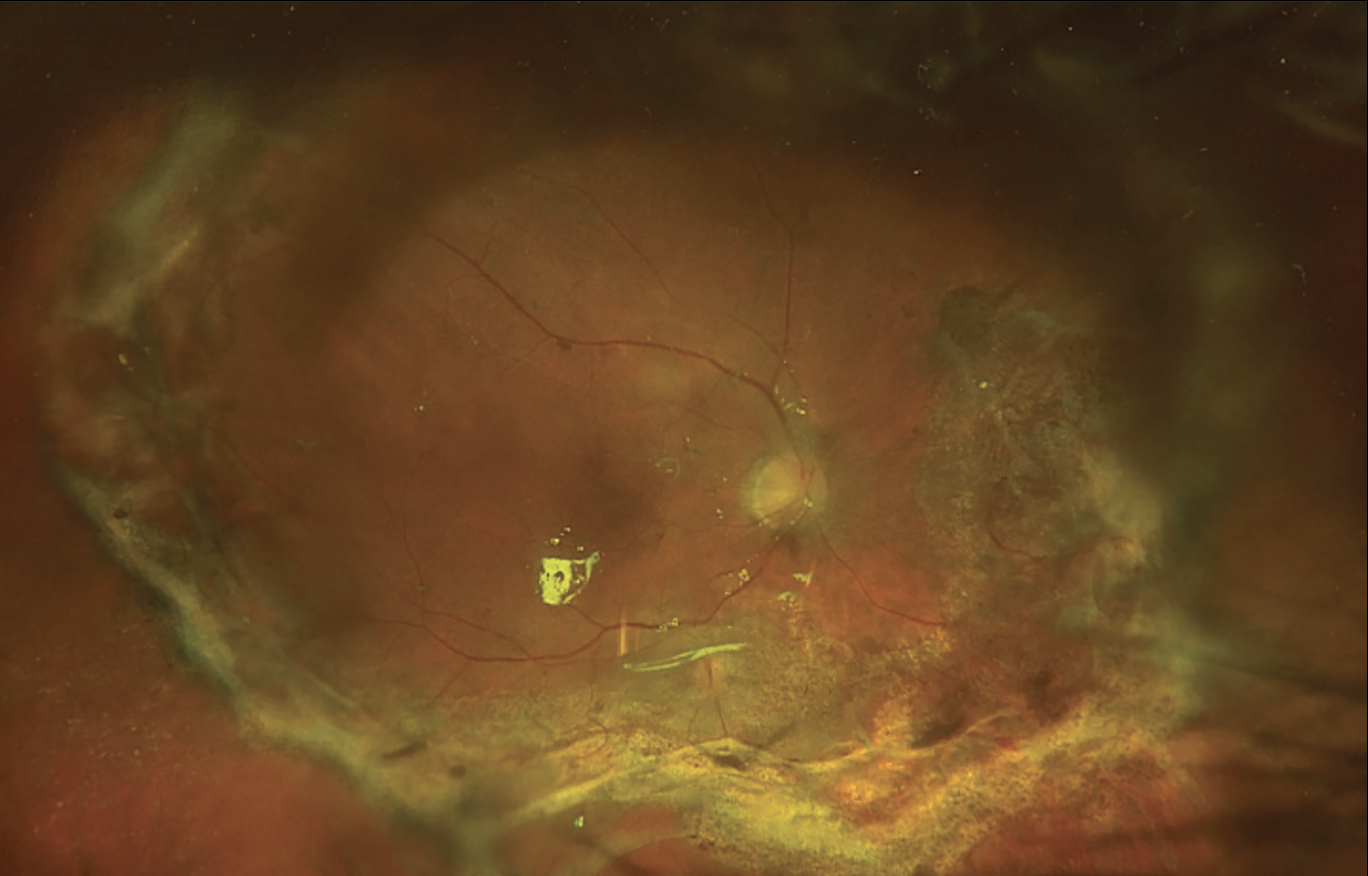

At the end of the surgery, vent the air, reduce the air infusion pressure and supplement the silicone oil fill because some silicone is always lost during the surgery due to inserting and removing the instruments, removing membranes and draining the subretinal fluid (Figure 2). We believe that this technique works because infusing air pushes silicon oil onto the retinal surface, creating more tension, which allows for drainage.

| Figure 2. The same recurrent retinal detachment from Fig. 1, secondary to proliferative vitreoretinopathy after surgery. |